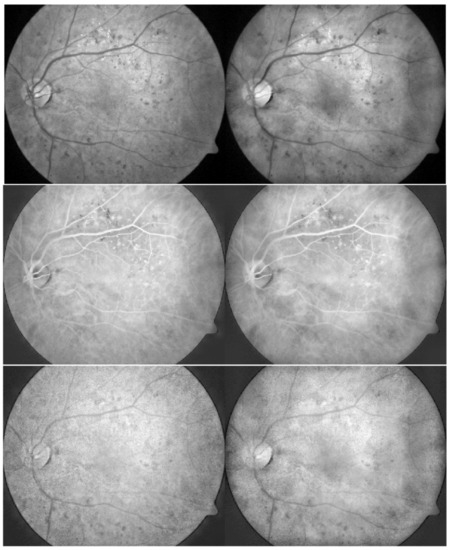

From the statistical information evaluation shown above, the proposed method performed well. However, the visual assessment would secure the statistical results for the experiment. Figure 7, Figure 8, Figure 9 show the outcomes from DiaretDB0 and STARE datasets, where each row provides an image from the dataset, and each column presents the method of the enhanced image. By starting from the first column, the original, the images were enhanced with CLAHE [3], scaling [9], ETHE [10], IETK [11], LCA [8], and the proposed method, respectively. In Figure 7, CLAHE images increase the contrast of the original images, yet they seem slightly darker. Although the scaling technique results in similar unacceptable percentage numbers to the proposed method, they differ when compared visually. The scaling technique leads to good quality in color brightness and color balance, but the contrast grades are low, whereas the proposed method provides better contrast. ETHE enhances a good contrast as the vessels separated clearly from the other parts; however, it led to unnatural color in the retinal image. IETK gives the brightest and most colorful result so that the vessels are easy to spot as they are in red color, which is different than those in the aforementioned three methods with brownish vessel color. LCA also gives good contrast and overall brightness result with a brownish tone but is less colorful. However, a great colorfulness does not imply to be most suitable for this kind of image as other factors such as the overall brightness and color balance in the RGB channels are also important. The proposed method results in good contrast, brightness, color balance, and colorfulness, yet it also maintains the overall brightness and brightness ratio between red, green, and blue compared to the standard. The blood vessels are easy to diagnose as it is in desired red color.

Figure 8 depicts abnormal lesions such as hard or soft exudates and hemorrhages. ETHE and IETK produce high saturation so that it might overexpose the information of those lesions as shown in Figure 8d,e, where exudate lesions are too saturate and too bright to maintain the information, and some hemorrhages are eradicated unintentionally.

Figure 8. The result of enhancement by different methods for 4 images (rows) from DiaretDB0 dataset. The columns represent (a) original, and outcome images are enhanced by (b) CLAHE, (c) scaling, (d) ETHE, (e) IETK, (f) LCA, and (g) proposed methods.

Symmetry 13 02089 g008

Figure 9. The result of enhancement by different methods for 4 images (rows) from STARE dataset. The columns represent (a) original, and outcome images are enhanced by (b) CLAHE, (c) scaling, (d) ETHE, (e) IETK, (f) LCA, and (g) proposed methods.